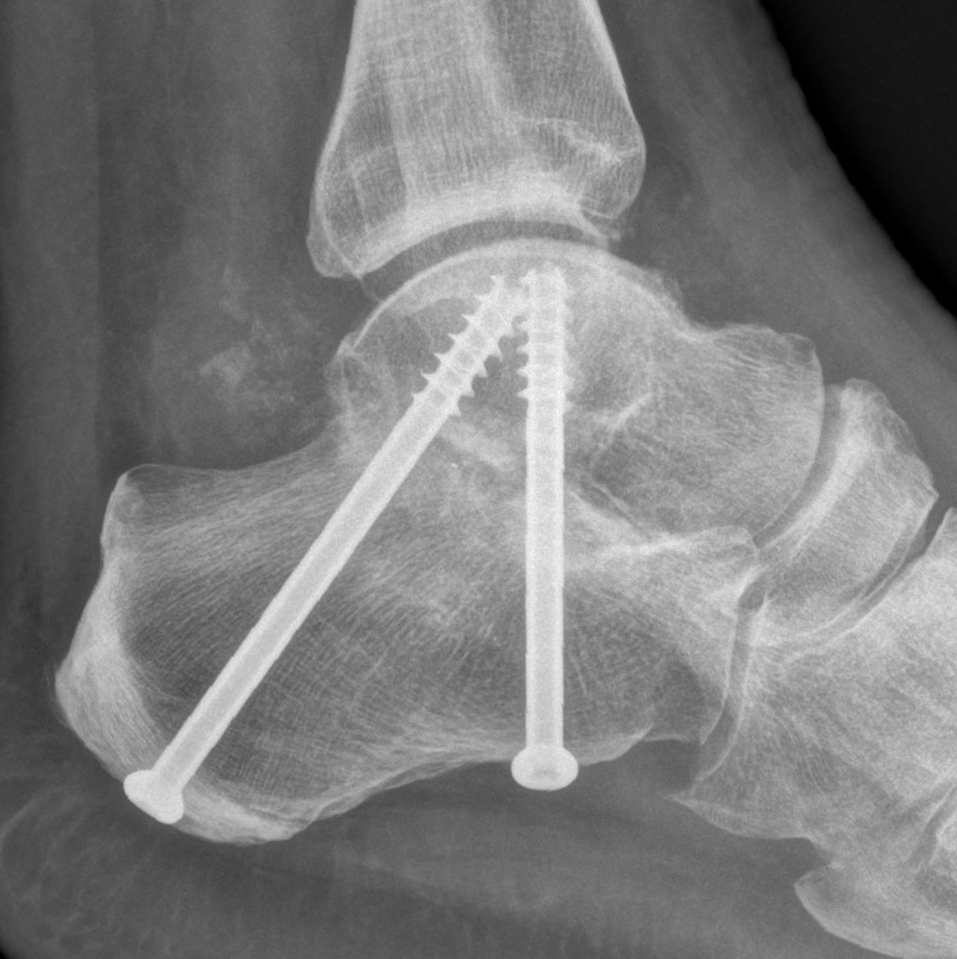

Fusion is permanently stiffening

the bones of a joint together with plates, screws and/or staples. This procedure is also known as arthrodesis.

This surgical procedure involves fusing one or more of the midfoot and hindfoot joints. A common combination is called a hindfoot "triple fusion".